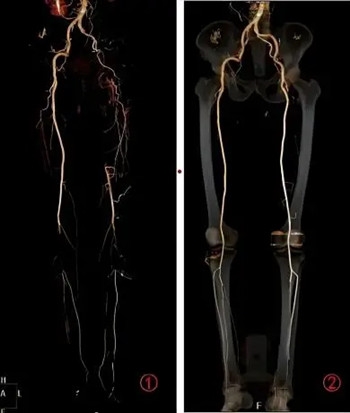

我们自己居家就可以先做简单的体格检查,可触摸双脚的温度是否对称或较上肢温度是否变凉,另外可触及自己双脚的足背动脉,看是否能触摸到搏动,如果搏动消失需尽快到血管外科就诊,可进一步行下肢血管彩超及CTA检查明确诊断,并根据检查结果制定治疗方案。

▲ 下肢动脉CTA检查